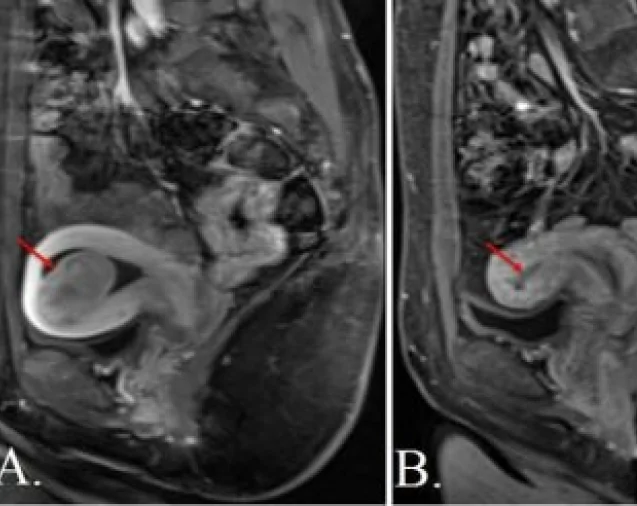

- Magnetic Resonance Imaging (MRI) – provides detailed images to assist with treatment planning

UFE works by blocking the small blood vessels that supply fibroids, causing them to shrink over time. The procedure is performed using a tiny catheter inserted through the wrist or groin, without large incisions or visible scarring.